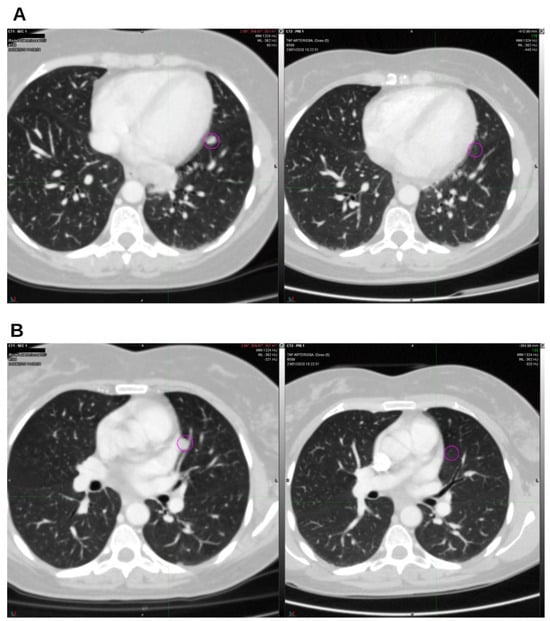

Integrative Use of Cannabidiol, Melatonin, and Oxygen–Ozone Therapy in Triple-Negative Breast Cancer with Lung and Mediastinal Metastases. A Case Report

Background and Clinical Significance: Breast cancer is the most frequent malignancy in women. Metastatic breast cancer is considered a treatable but incurable condition, with a median overall survival of only 2–3 years. Among its subtypes, triple-negative breast cancer (TNBC) accounts for a high proportion of breast cancer-related deaths. It is characterized by an aggressive clinical course, early recurrence, and a strong propensity for visceral and brain metastases. Case Presentation: We report the case of a Caucasian woman who developed systemic disease recurrence with lung and mediastinal lymph node metastases, occurring two years after her primary diagnosis and treatment for TNBC. The patient received three months of chemotherapy combined with an adjuvant integrative protocol consisting of melatonin, cannabidiol, and oxygen–ozone therapy. This combined approach led to the complete disappearance of the lung nodules. Subsequently, stereotactic radiotherapy was performed and, in association with the ongoing integrative treatment, resulted in a significant reduction in mediastinal adenopathy. Introduction of immunotherapy, supported continuously by the same adjuvant strategy, achieved a complete and durable remission. Strikingly, the patient remained disease-free five years after the diagnosis of lung and mediastinal metastases. Conclusions: This clinical case highlights the potential benefit of using melatonin, cannabidiol, and oxygen–ozone therapy as part of an integrative approach in patients with aggressive metastatic TNBC. While it is not possible to establish causality from a single case, the sustained remission observed suggests that such unconventional adjuvant strategies could play a supportive role in enhancing the efficacy of standard oncologic therapies. Full article

Figure 1